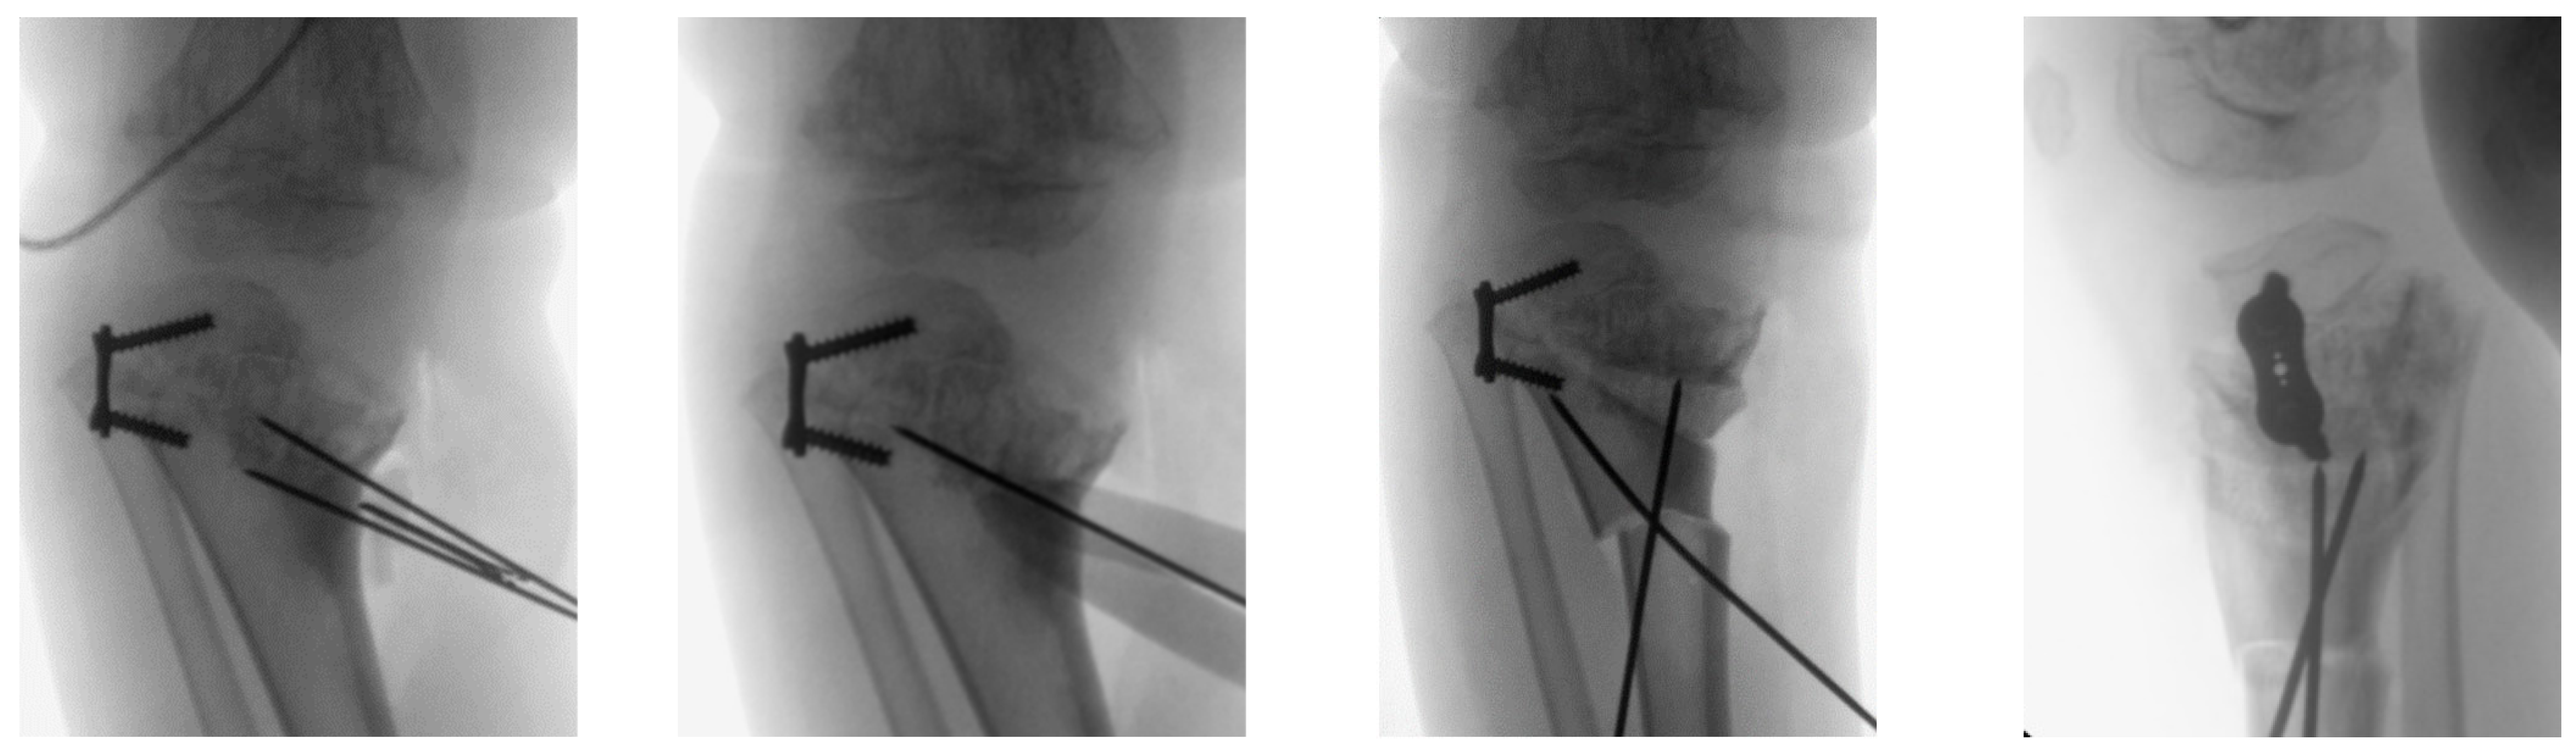

2.4. Design and 3D-printing of the Patient-Specific Surgical Instrument

2.5. Design and Processing of the Patient-Specific Bone Allograft

3. Results